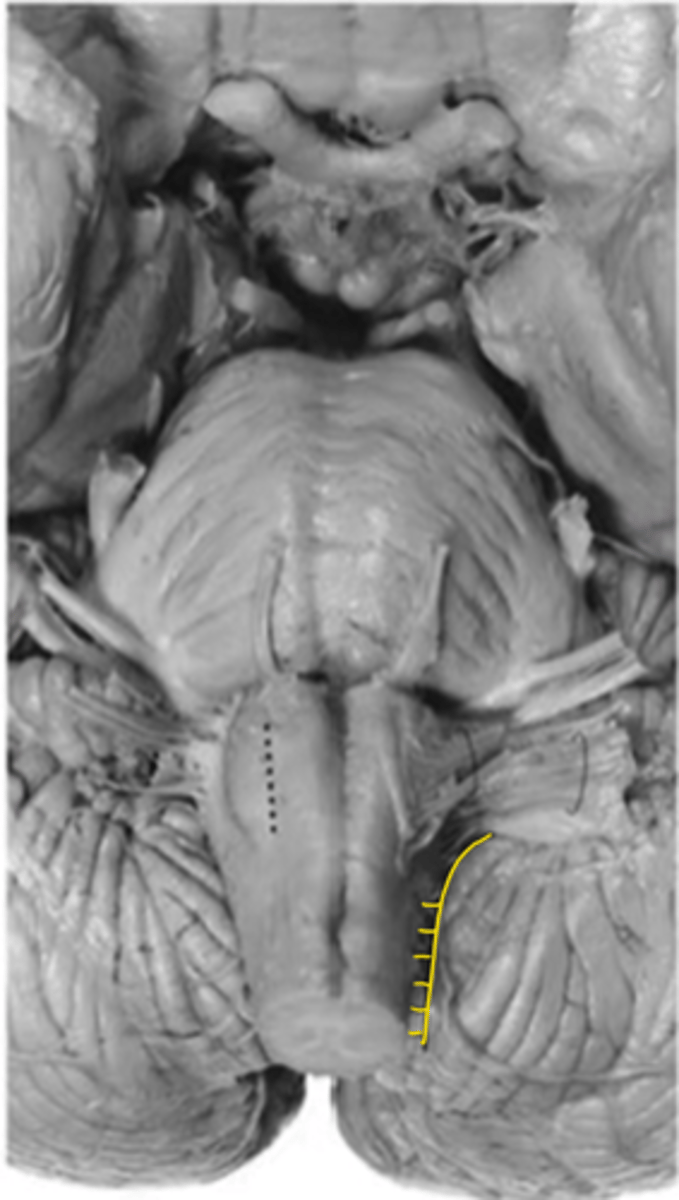

medulla

ID the area

open medulla

closed medulla

posterior median sulcus

ID the sulcus

posterior intermediate sulcus

posterior lateral sulcus

gracile tuberle

ID the structure

cuneate tubercle

gracile fasciculus

ID the fibers

cuneate fasciculus

superior cerebellar peduncles

inferior cerebellar peduncles

ID the brainstem level